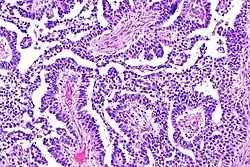

A micrograph of the primitive neuroepithelium of an immature teratoma, showing encapsulated mass.

Teratoma are most common germ cell tumor of ovary. Teratomas can be divided into two types: mature teratoma (benign) and immature teratoma (malignant). Immature teratomas contain immature or embryonic tissue which significantly differentiates them from mature teratomas as they carry dermoid cysts.[5] It is commonly observed in 15 to 19-year-old women and rarely in women after menopause.[6] Immature teratomas are characterized with a diameter of 14–25 cm, encapsulated mass, cystic areas, and occasional appearance of hemorrhagic areas.[7] The stage of immature teratomas is determined depending on the amount of immature neuroepithelium tissue detected.[5]